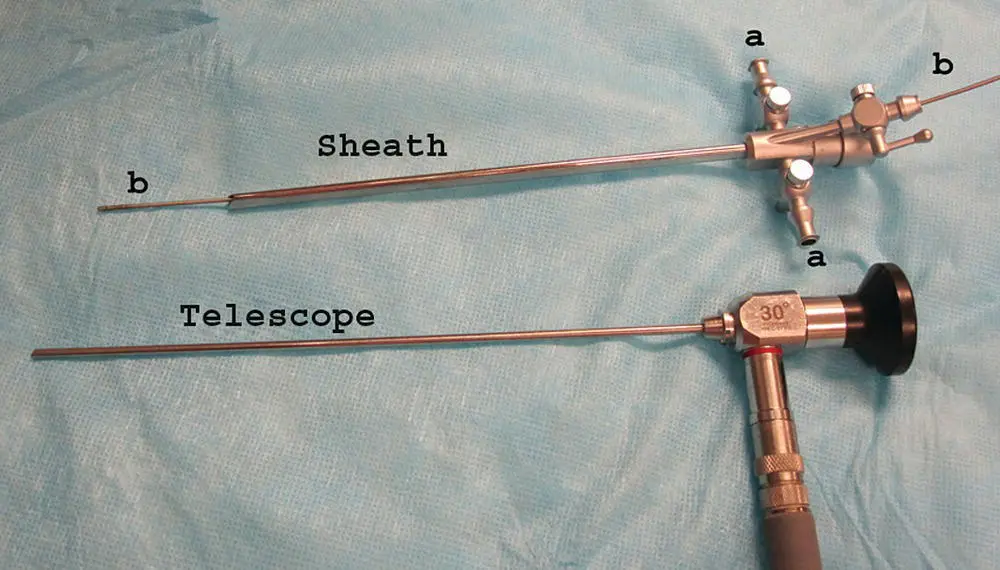

Before entering the nasal cavity, the endoscope is placed against the skull and measured to the level of the medial canthus of the eye to approximate the position of the cribriform plate. A piece of tape is applied to the instrument at this length, and the equipment should not be passed further than this point to avoid penetrating through the cribriform plate into the brain case. The normal nasal cavity is made up of scrolls of turbinates comprising the dorsal, middle, and ventral concha. The mucosa is generally pink, with a pale sheen of serous secretions coating the smooth epithelial surface ( Figure 2.12). The primary changes to look for during rhinoscopy are mucosal hyperemia, mucus accumulation, epithelial irregularities, turbinate destruction that is visualized as increased space between turbinates, or a mass effect that reduces space in the nasal cavity. After the initial visual inspection and when the cribriform plate is intact, nasal drops containing oxymetazoline or phenylephrine can be dropped or sprayed into the nasal cavity to create vasoconstriction. This will cause swollen and hyperemic mucosa to blanch and shrink, thus changing the overall appearance of the mucosa, but allowing improved access in some situations. Topical anesthetic drops or a misted spray of tetracaine can also be used to help reduce the stimulation caused by rhinoscopy, although this is variably effective.

Figure 2.12 Normal nasal turbinates in (a) the dog and (b) the cat.